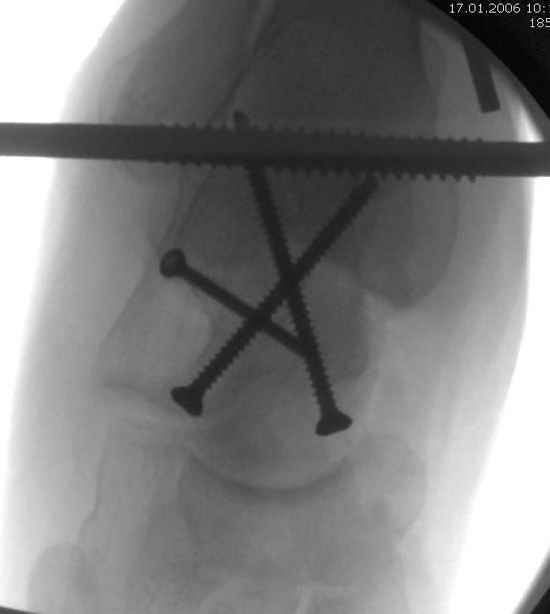

Для доступа к задне-медиальному суставному фрагменту я выполнил косую остеотомию внутренней лодыжки у её основания -получается хороший доступ к голеностопу, адекватный обзор и возможность восстановить суставную поверхность. фрагмент фиксировал двумя 3,5 мм спонгиозными винтами с неполной резьбой, *утопив* головки винтов в кость. Аналогичная фиксация и двумя тягловыми винтами и внутренней лодыжки. \в качестве альтернативы для

фиксации фрагмента тарана можно было бы использовать и герберт винты, но по организационным причинам :-(( набора не оказалось под рукой).

Вдогонку по поводу перелома таранной кости, больная 81, не страдает диабетом, перелом закрытый, в первый же день поступления ограничились временным наружным фиксатором (как на снимке).

Из-за отека на стопе тактика лечения у всех была

одинаковая: временная наружная фиксация до спадения отека, при изолированных переломах они выписывались домой и через дней 7 госпитализировались на оперативное лечение.

Примеры на снимке...